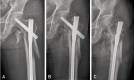

Materials and methods: Twenty-one consecutive patients with severe subtrochanteric femoral fractures who had undergone intramedullary fixation using long-PFNA II between March 2010 and March 2013 were followed-up for over 12 months. Their mean age was 64.8 years old (range, 43-85 years). Sixteen of 22 cases were high energy trauma. According to Seinsheimer's classification, 5 cases were type IV and 16 cases were type V. For radiological assessment, time to union, change of neck-shaft angle, sliding length, tip-apex distance (TAD) and leg length discrepancy (LLD) were measured. For clinical evaluation, a modified Koval index was investigated.

Results: Mean operation time was 96 minutes. An average decrease of neck-shaft angle was 4.5°. The average sliding length of the helical blade was 4.2 mm. Average LLD was 3.0 mm, and TAD was 23.0 mm. Mean modified Koval index score at final follow-up was 4.6 points. All the 21 subtrochanteric fractures healed uneventfully on an average of 24.2 weeks (range, 18-30 weeks).